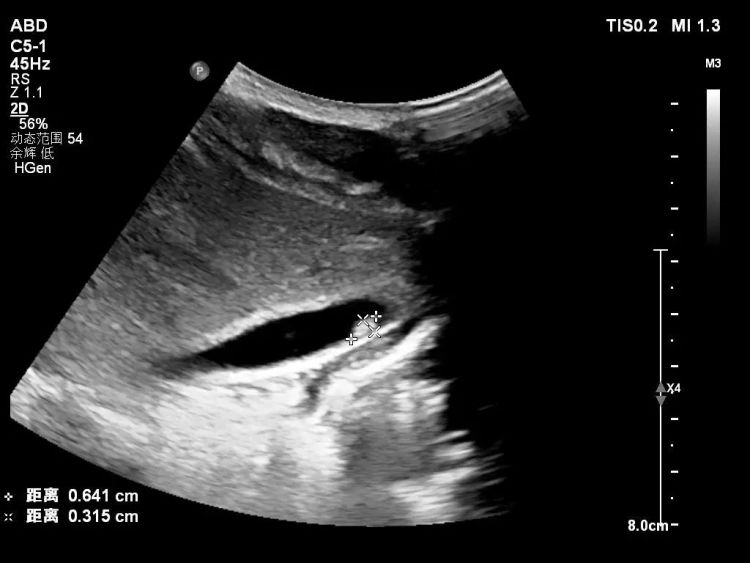

在医生的建议下,小凯一家三口都做了寄生虫相关检查,结果显示,三人血常规中嗜酸性粒细胞都异常升高!小凯还有肝功能异常,彩超显示肝内有片状低回声区,肝门淋巴结肿,妈妈的大便中检出肝吸虫卵!